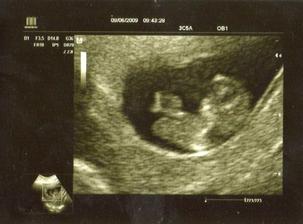

Dne 30.4. jsem si udělala testík,který mi připadal uplně zbytečný normálně se mi menstruace opozdila o několik dní,ale tentokrát to bylo asi podezdřele dlouhé opoždění.Dala jsem na radu kamarádky a test si udělala,co to bylo za velikánnské překvapení a šok zároveň to se ani nedá popsat 🙂Moje dcerka Sárka si musela myslet,že jsem se zbláznila 😀

Když jsem tu zprávu oznámila manžílkovi byl naprosto nadšený a na vysvětlení jak to,že mě neinformoval o tom,že chce udělat bez mého vědomí mimíska mi řekl,že na něj hold přišlo jaro 🙂